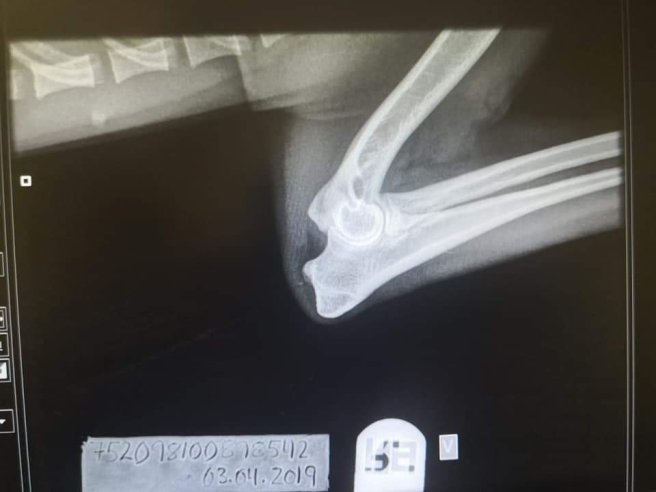

Hinnih fria armbågar ❤ april 16, 2019april 16, 2019 ~ kelpiecarro Grattis Hanne och Hinnih ❤ som också sedan tidigare är röntgad med A på höfter Dela detta: Dela på X (Öppnas i ett nytt fönster) X Dela på Facebook (Öppnas i ett nytt fönster) Facebook Gilla Laddar in … Relaterade